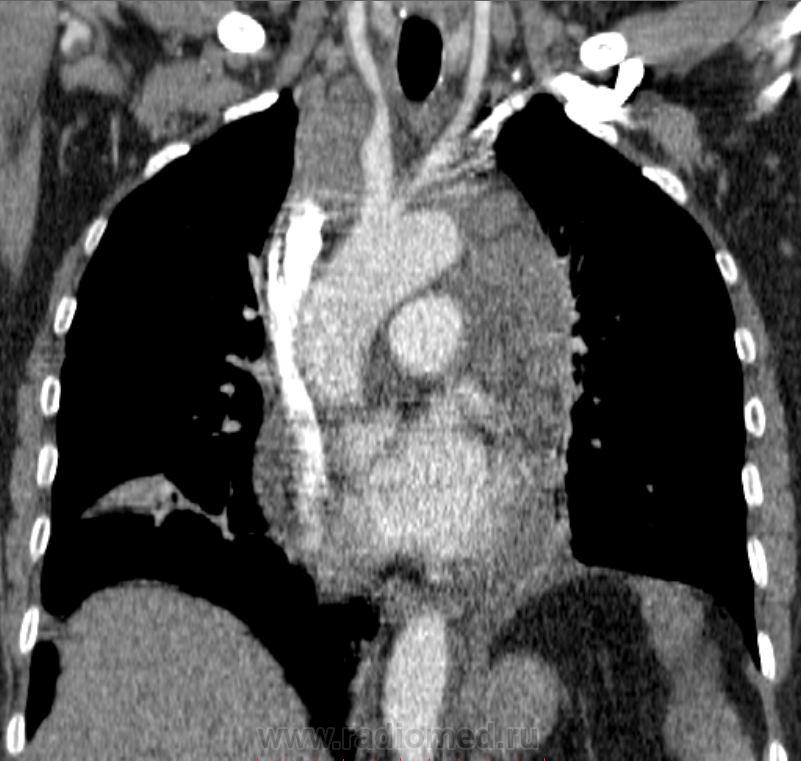

Лимфома с преимущественным поражением переднего средостения, двусторонний гидроторакс, субсегментарные ателектазы, поражение лимфоузлов прекардиальной клетчатки.

Получается, 1-6 группы поражены в представленном случае.

Злокачественная лимфома переднего средостения, наиболее вероятно, неходжкинская лимфома, двусторонний плевральный выпот.